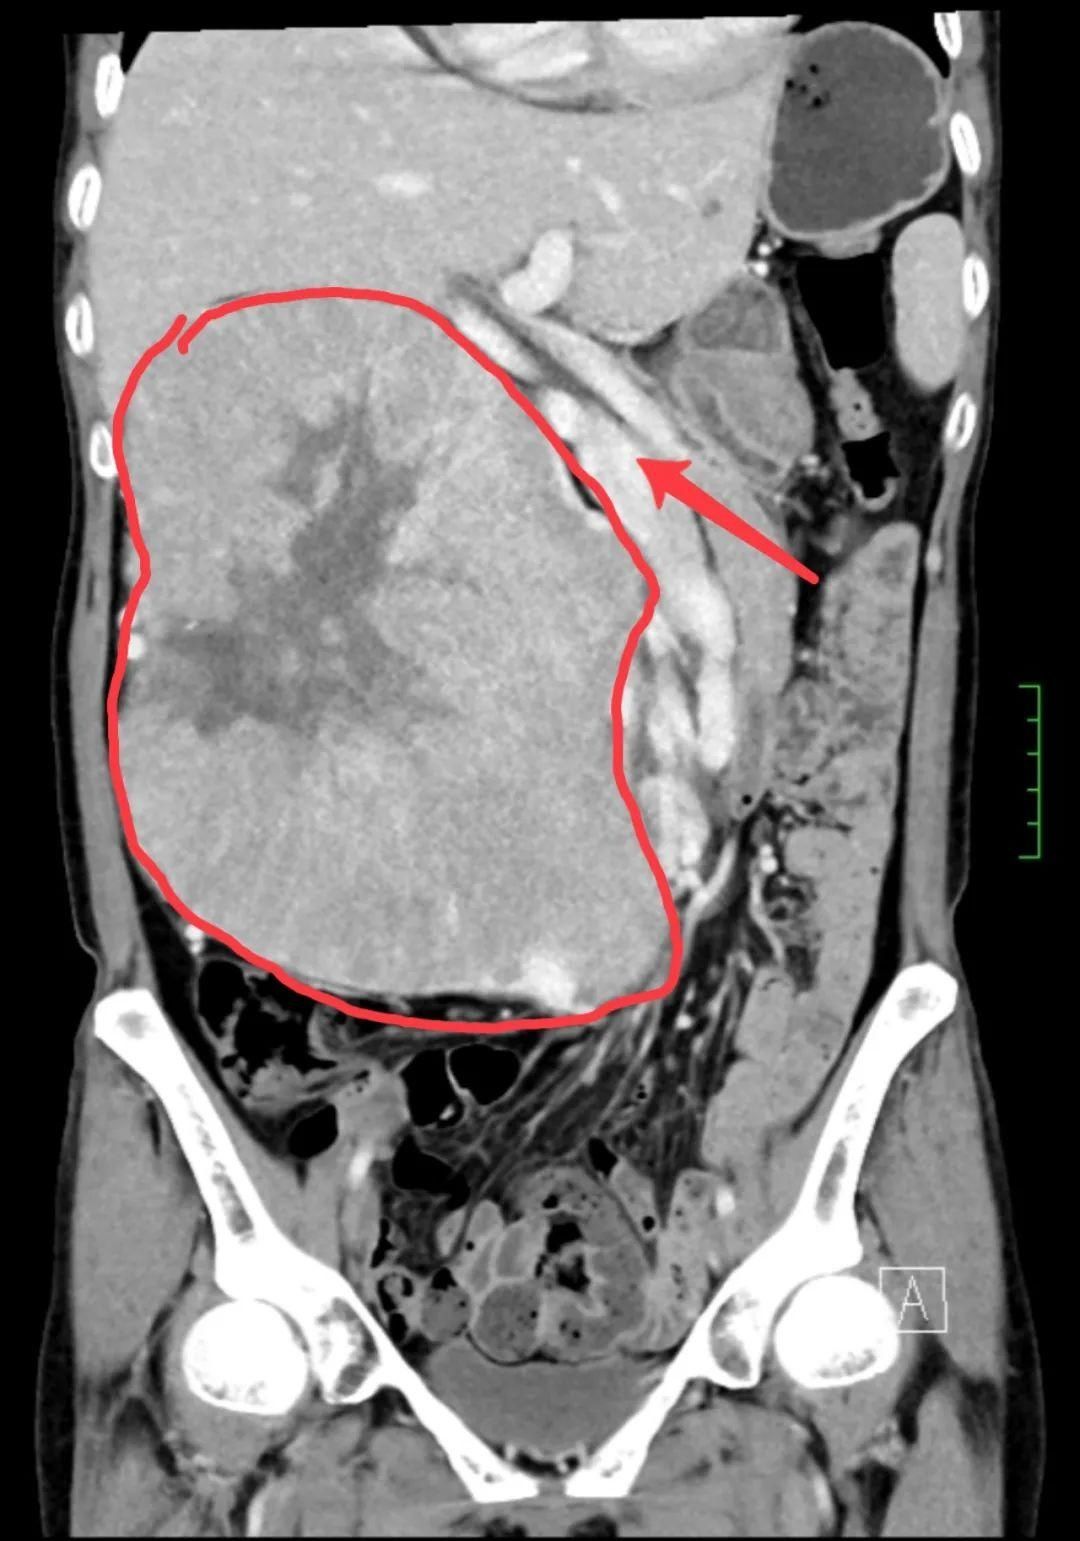

入院后,王建松副主任医师医疗小组详细询问病史并完善相关检查,泌尿系增强CT及血管成像提示:右肾巨大占位,直径约为20cm,足有西瓜大小。由于肿瘤体积过大,腹中其他脏器被挤压移位,失去了正常的解剖结构;肿瘤还压迫下腔静脉、腹主动脉;同时,肿瘤血运丰富,手术难度与风险极高,术中稍有不慎就会造成大出血。